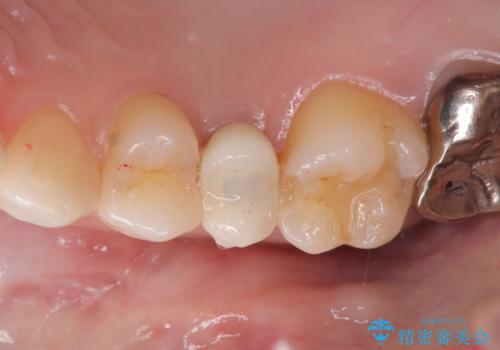

インプラント埋入手術は1回で全て行い、2ヶ月後にはセラミック治療で、審美回復と機能回復をしました。

来院回数が少なく、しっかり食事もできるとの事で非常に喜んで頂けました。